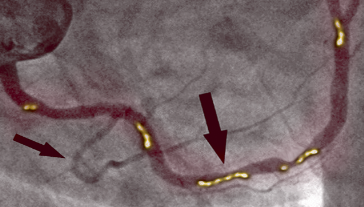

PRED

Na sliki levo vidimo zoženje desne koronarne arterije pri 66-letnem moškem. Vidno je znatno zoženje v proksimalnem odseku, ki ga povzroča poapnela aterosklerotična leha in ki ovira pretok krvi.

PO

Na sliki desno vidimo, kako je videti očiščena koronarna arterija, že brez sledi poapnele aterosklerotične lehe. Ni oblog holesterola. Kri teče prosto in oskrbuje s kisikom vse organe.